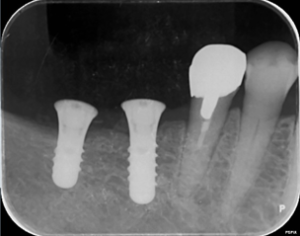

左下の奥歯のレントゲン写真です。

矢印部の骨が炎症にて吸収されていました。

歯ぎしりによる歯の摩耗で細菌の感染を受けて炎症が起こっていました。そのため、歯の根の治療を行いました。

左下の奥歯の根の治療後のレントゲン写真です。

矢印部にみられた骨の吸収像はなくなり、歯ぐきの炎症も改善しました。